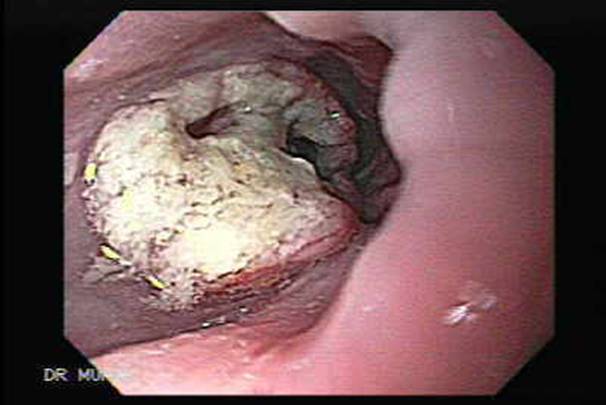

• Обследование эндоскопическим методом. Дает возможность установить причину, по которой нарушена функция глотания, увидеть размер и распространенность новообразования, сделать биопсию подозрительной области.

image010.jpg Эндоскопическая картина аденокарциномы

image012.jpg Эндоскопическая картина плоскоклеточного рака